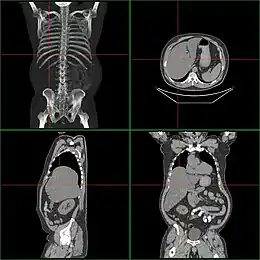

Tomographie d'une hépatomégalie.

En cas de difficulté pour palper, il est possible de réaliser une échographie abdominale. Cette dernière permet d'affirmer l'hépatomégalie lorsque la distance séparant le sommet du foie et son bord inférieur est supérieure à 12 cm, sur la ligne médioclaviculaire. Elle permet aussi de rechercher la présence d'une tumeur , du rein, de la vessie, des voies biliaires ou du pancréas, une splénomégalie associée, des signes de stéatose ou de cirrhose.